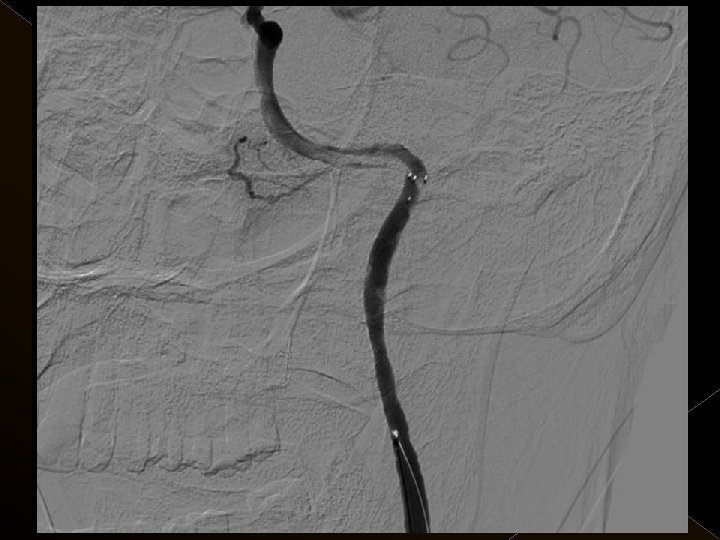

� İnme tedavisinde iv tpa uygulamasını takiben � intraarteriyel (İA) trombolitik tedavi (ia tpa ve ia mekanik trombolizis) � İA stent yardımı ile trombektomi yöntemleri kullanılarak tedaviye cevap ve komplikasyonlar araştırıldı.

KOMPLİKASYONLAR Ponksiyon bölgesi komplikasyonları � Trombektomi stentine ait komplikasyon (*1) � Diseksiyon(*2) � Karotikokavernöz fistül (‘ 1) � Hemorajik komplikasyonlar(‘ 5) Semptomatik-nonsemptomatik � İskemik komplikasyonlar (3) � Reoklüzyon (2 i. a) � Kontrast madde nefropatisi �